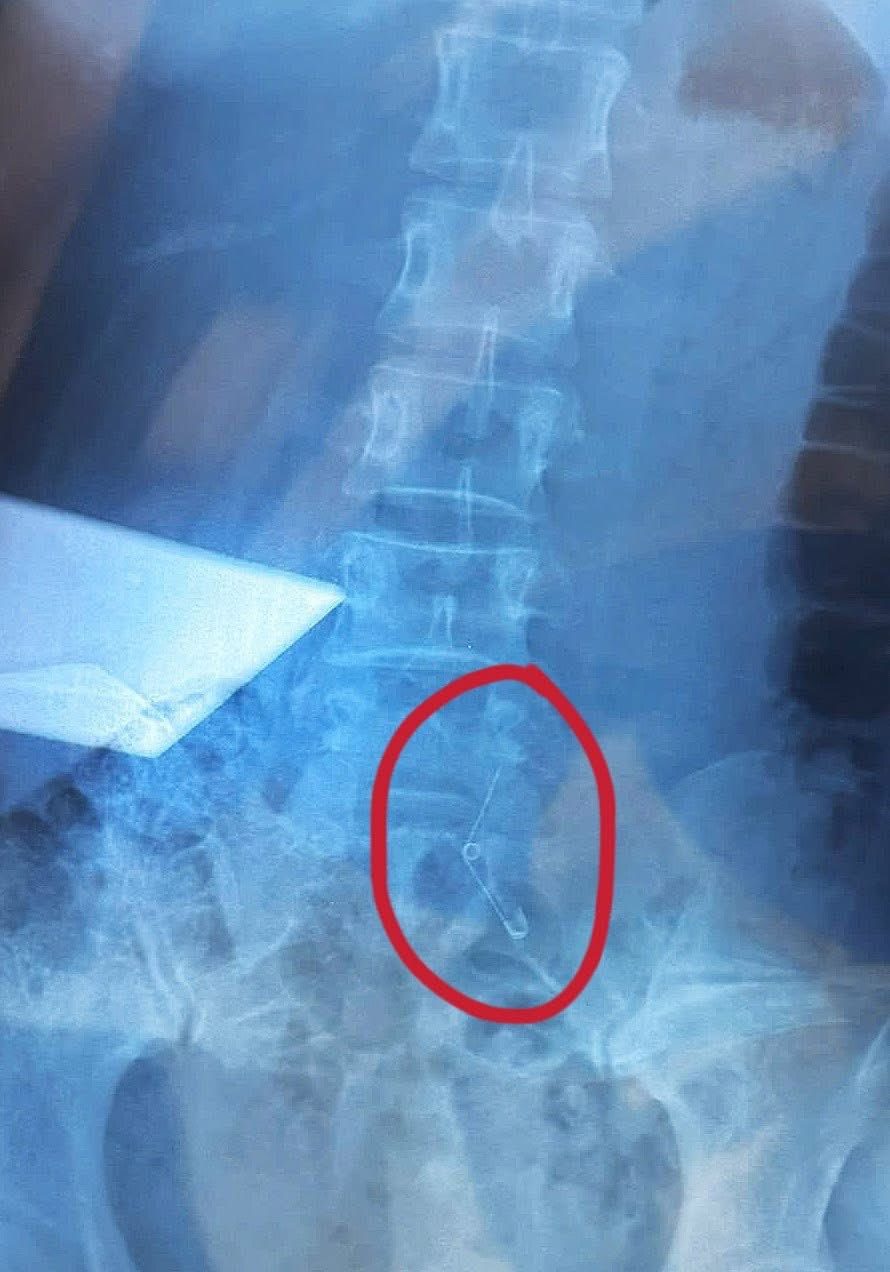

Trong một tình huống khó tin nhưng hoàn toàn có thật, một người phụ nữ đã gặp phải sự cố khi đang thưởng thức món ốc cùng với đồng nghiệp. Trong lúc ăn, cô bất ngờ cảm thấy nghẹn, nhưng vẫn tiếp tục thưởng thức món ăn yêu thích. Chỉ đến khi nhìn xuống, cô mới hoảng hốt nhận ra chiếc ghim băng dùng để khêu ốc đã không còn ở đó, và cô đã nuốt phải nó.

Ngay trong đêm, người phụ nữ này đã được đưa đến bệnh viện và trải qua gần 6 tiếng đồng hồ trong phòng phẫu thuật để các bác sĩ mổ dạ dày và lấy chiếc ghim ra. Rất may mắn, chiếc ghim chưa gây ra tổn thương cho thực quản.

Sau ca phẫu thuật, cô vẫn chưa thể hiểu nổi bằng cách nào mình có thể nuốt trôi một vật sắc nhọn như vậy mà không hề cảm thấy đau, thậm chí còn tiếp tục ăn uống như chưa có chuyện gì xảy ra.